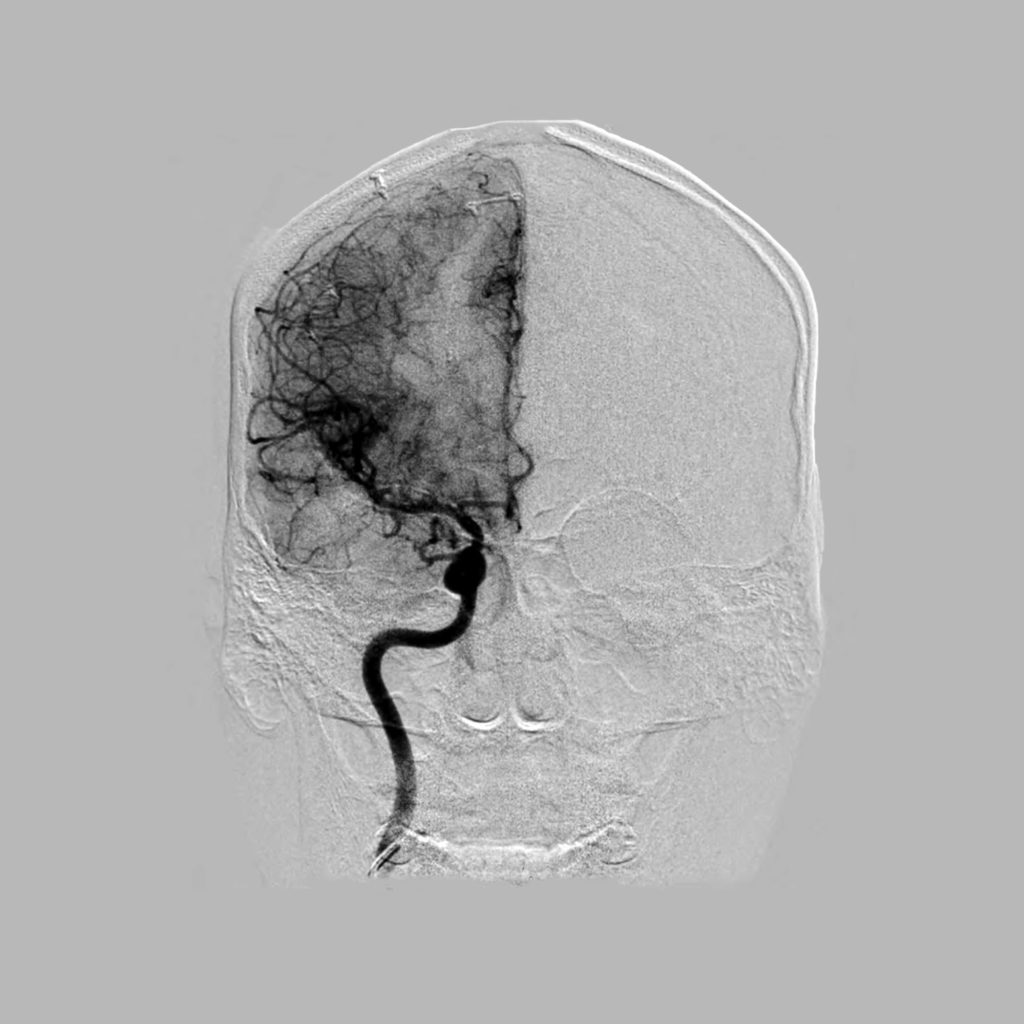

What is a Brain Angiogram and why is it done? What Information Does An Angiogram Provide Doctors use angiograms to help diagnose medical conditions related to the arteries or heart. An angiogram is a minimally invasive procedure to identify or confirm artery and vein abnormalities, such as blockages, narrowing, or abnormal connections. An angiogram is an effective procedure to diagnose and treat disorders that commonly affect the blood supply of the heart and brain. Angiography allows. What Information Does An Angiogram Provide.

Brain & Spine Foundation Angiogram of the brain What Information Does An Angiogram Provide An angiogram is a minimally invasive procedure to identify or confirm artery and vein abnormalities, such as blockages, narrowing, or abnormal connections. It's usually done to see if a blood vessel is narrowed or. Doctors use angiograms to help diagnose medical conditions related to the arteries or heart. Angiography allows doctors to clearly see how blood flows into the heart.. What Information Does An Angiogram Provide.